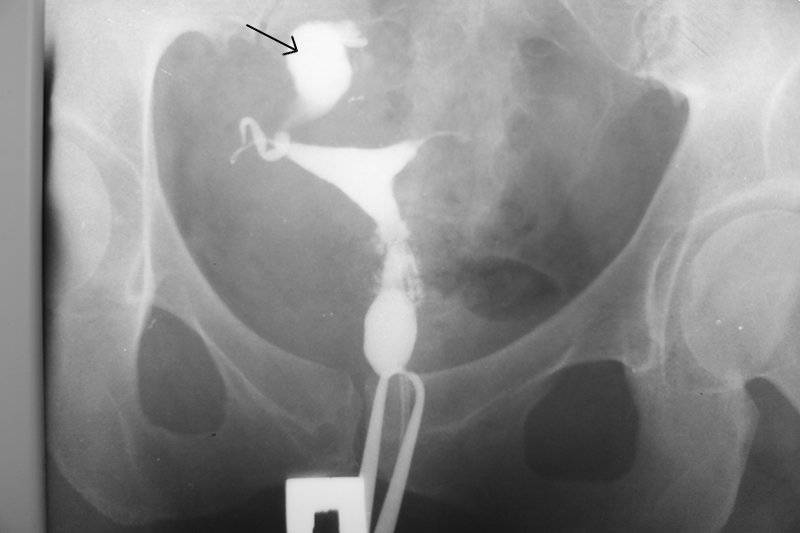

Гистеросальпингография: описание и фотографии